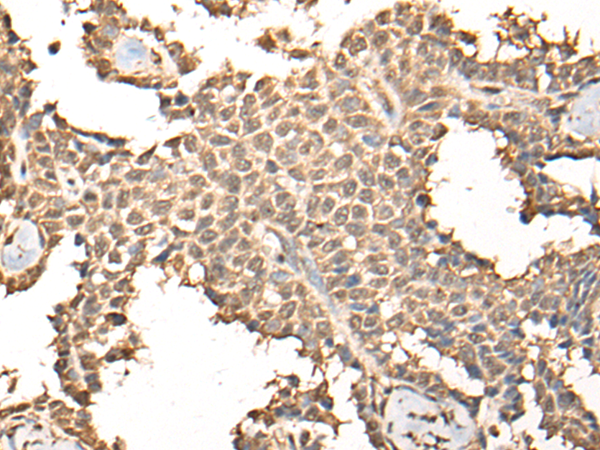

IHC positive control: |

Human ovarian cancer and human thyroid cancer |